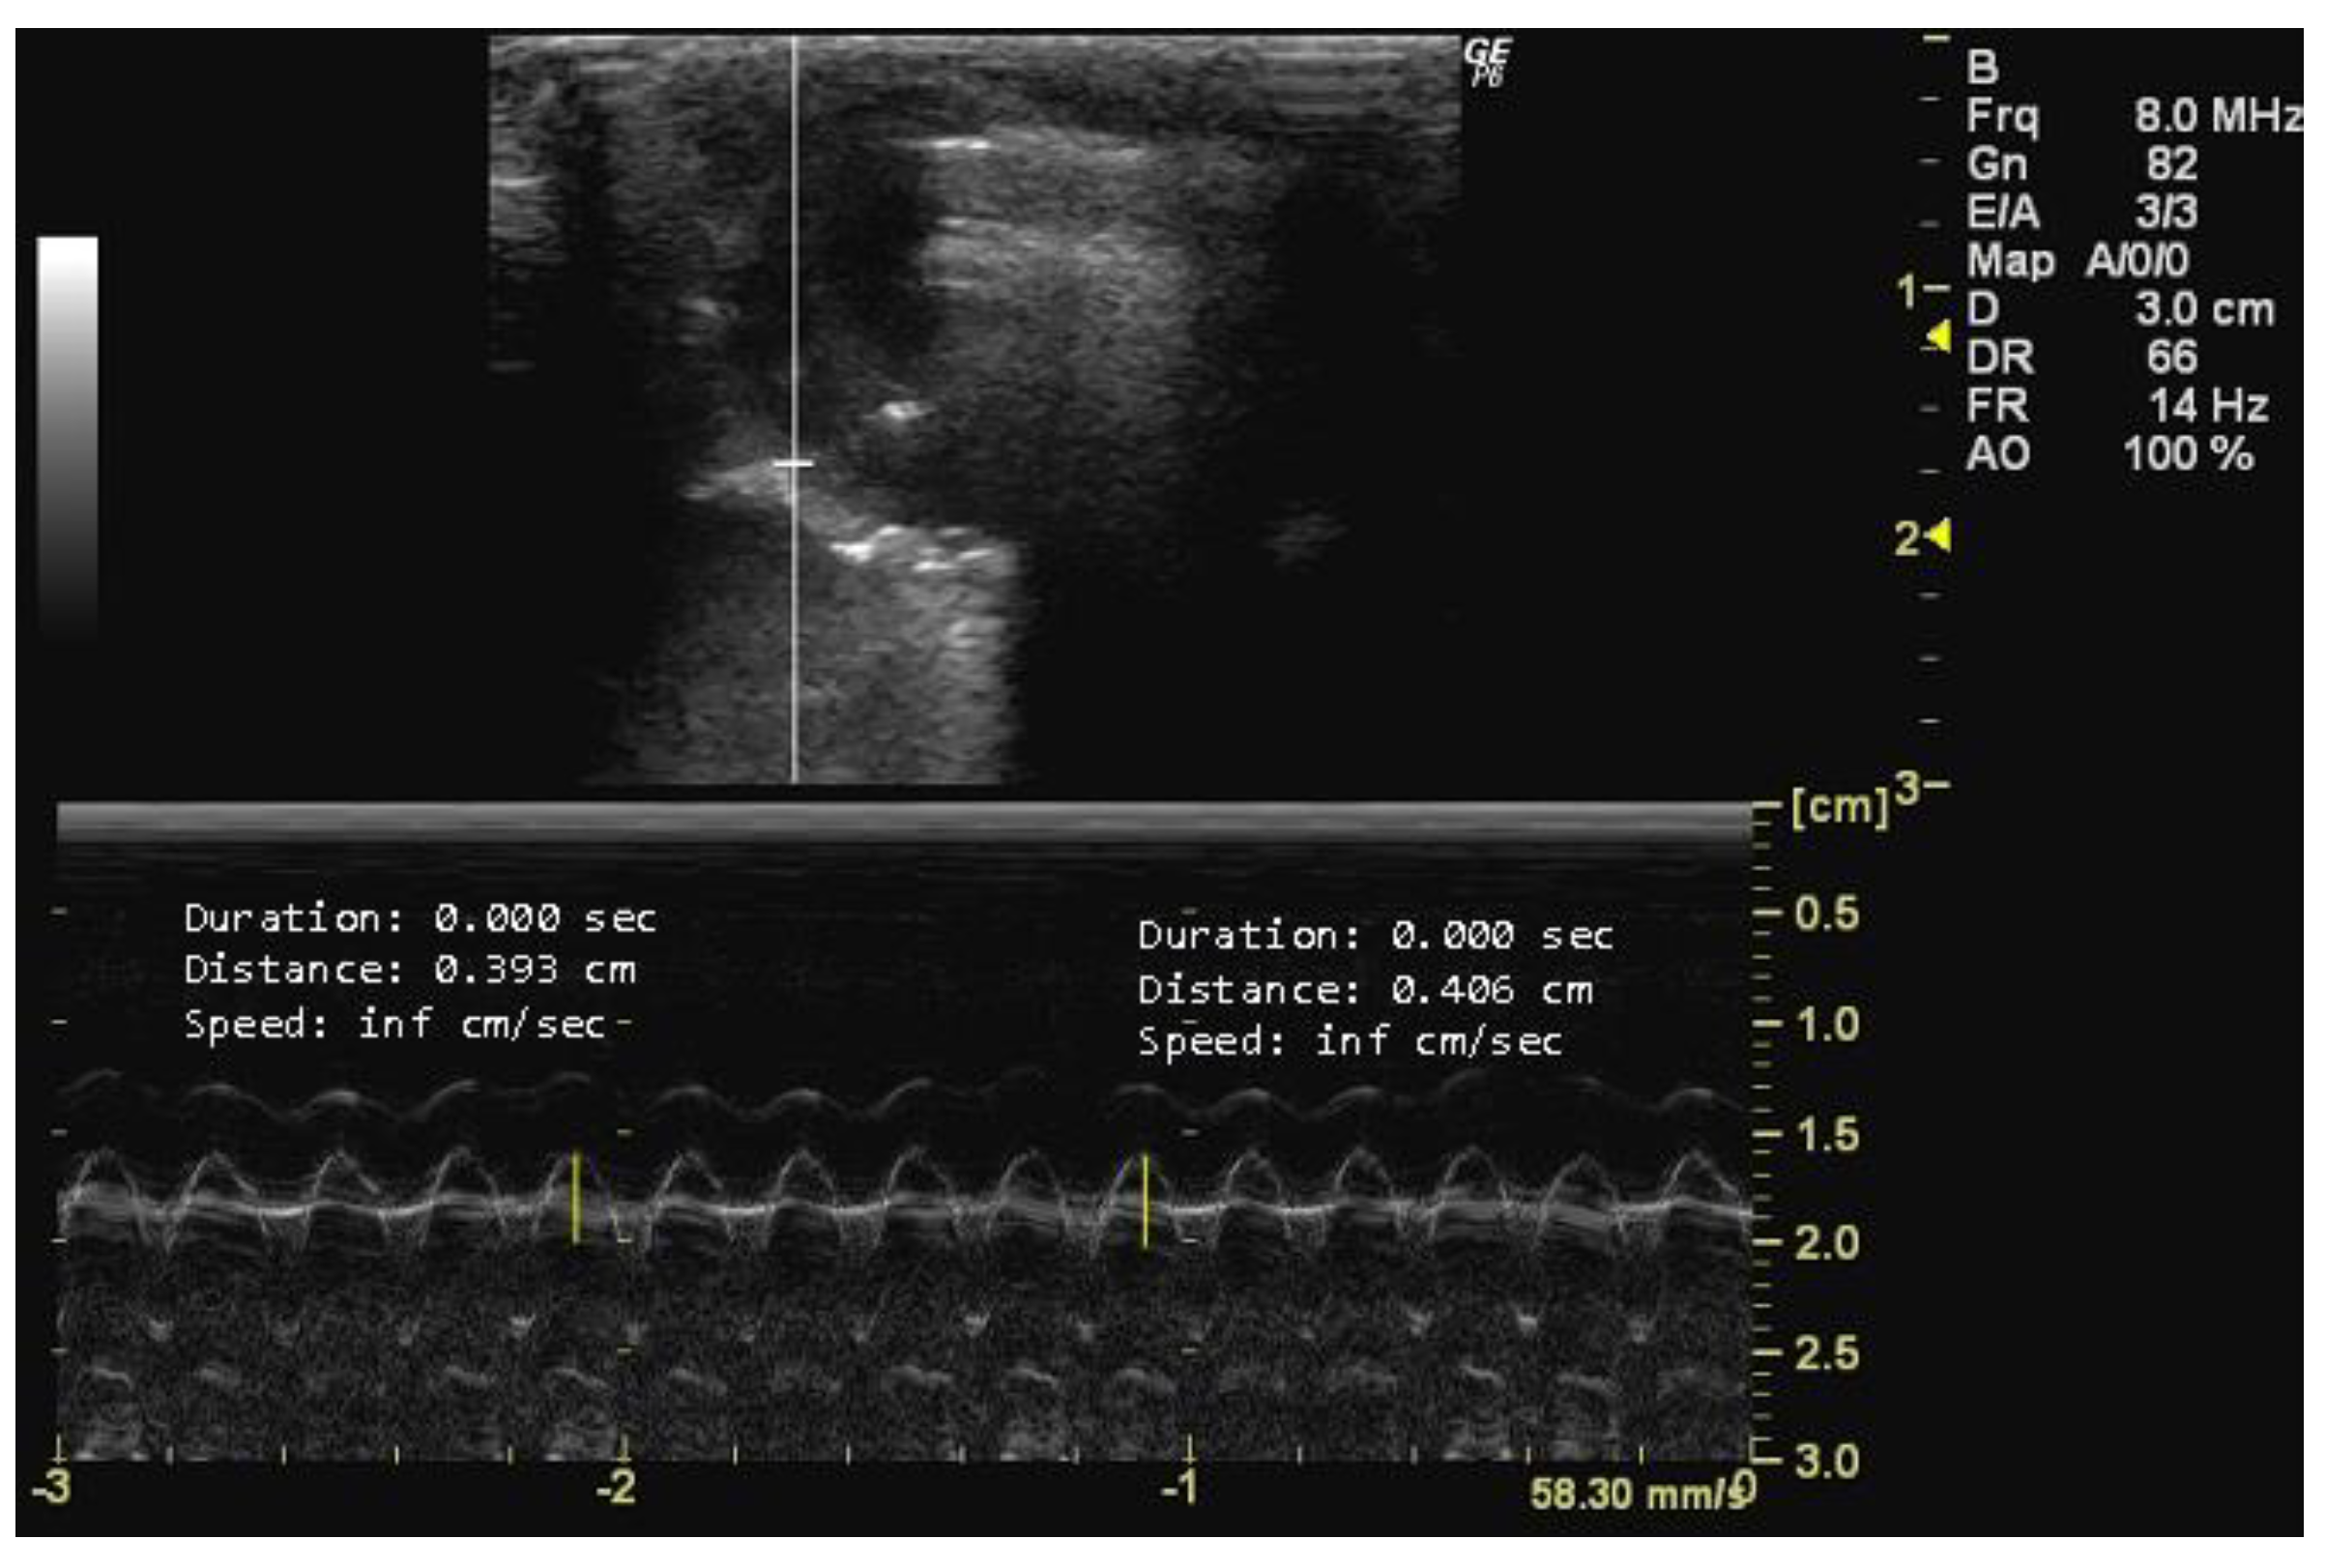

- How to measure HR

- How to measure D1 and D2